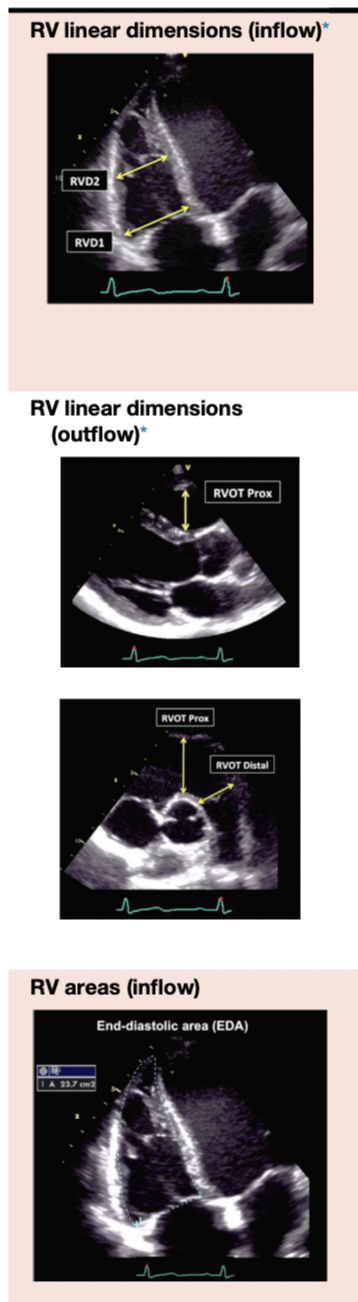

RV Measurements

- Cardiac Chamber에서 RV size를 측정하는 방법과 normal range입니다.

- RV wall thickness를 측정하는 방법이고, end-diastole에서 측정합니다.